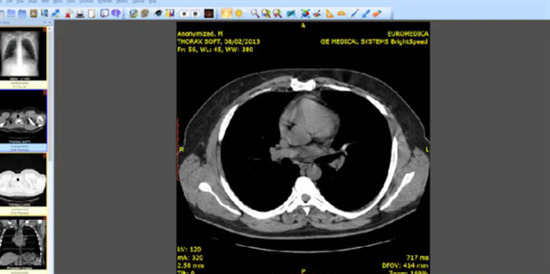

1.dicom格式是一个存储医疗图像的文件格式协议。dicom是医学数字成像和通信,是医学图像和相关信息的国际标准,它定义了质量能满足临床需要的可用于数据交换的医学图像格式。

2.dicom被广泛应用于放射医疗,心血管成像以及放射诊疗诊断设备,并且在眼科和牙科等其它医学领域得到越来越深入广泛的应用,在数以万计的在用医学成像设备中,dicom是部署最为广泛的医疗信息标准之一,当前大约有百亿级符合dicom标准的医学图像用于临床使用。